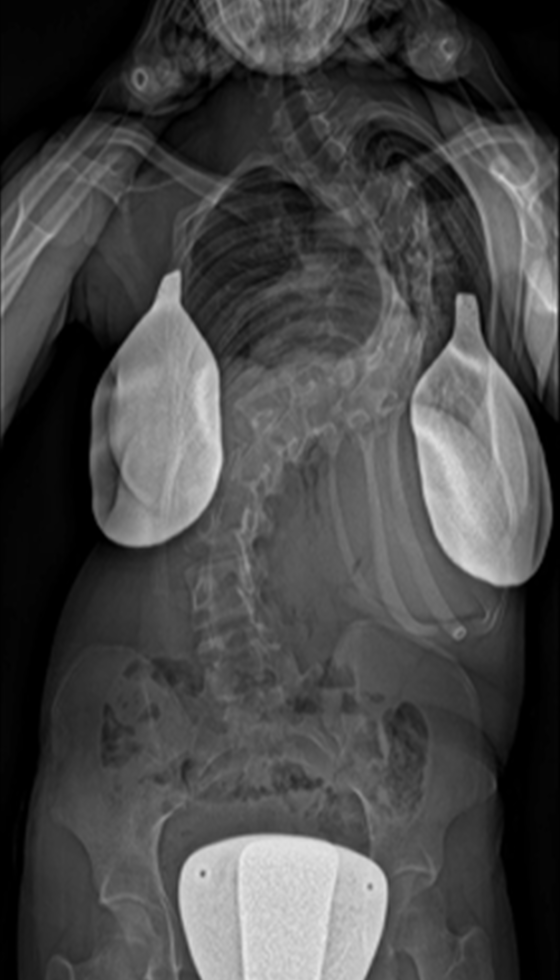

Gallery : Before - After